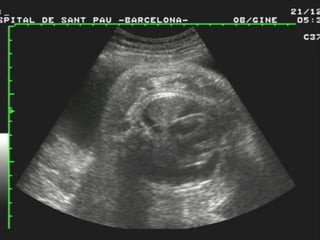

DISPLACIA ESQUELÉTICA

PACIENTE DE 29 AÑOS, IV GESTA, PARA III

Y EMBARAZO DE 32 SEMANAS A LA QUE

SE ENCONTRARON LOS SIGUIENTES

HALLAZGOS ECOGRÁFICOS:

HF,

MACROGLOSIA,

DISPLASIA ESQUELÉTICA DEL TIPO

ACONDOPLASIA